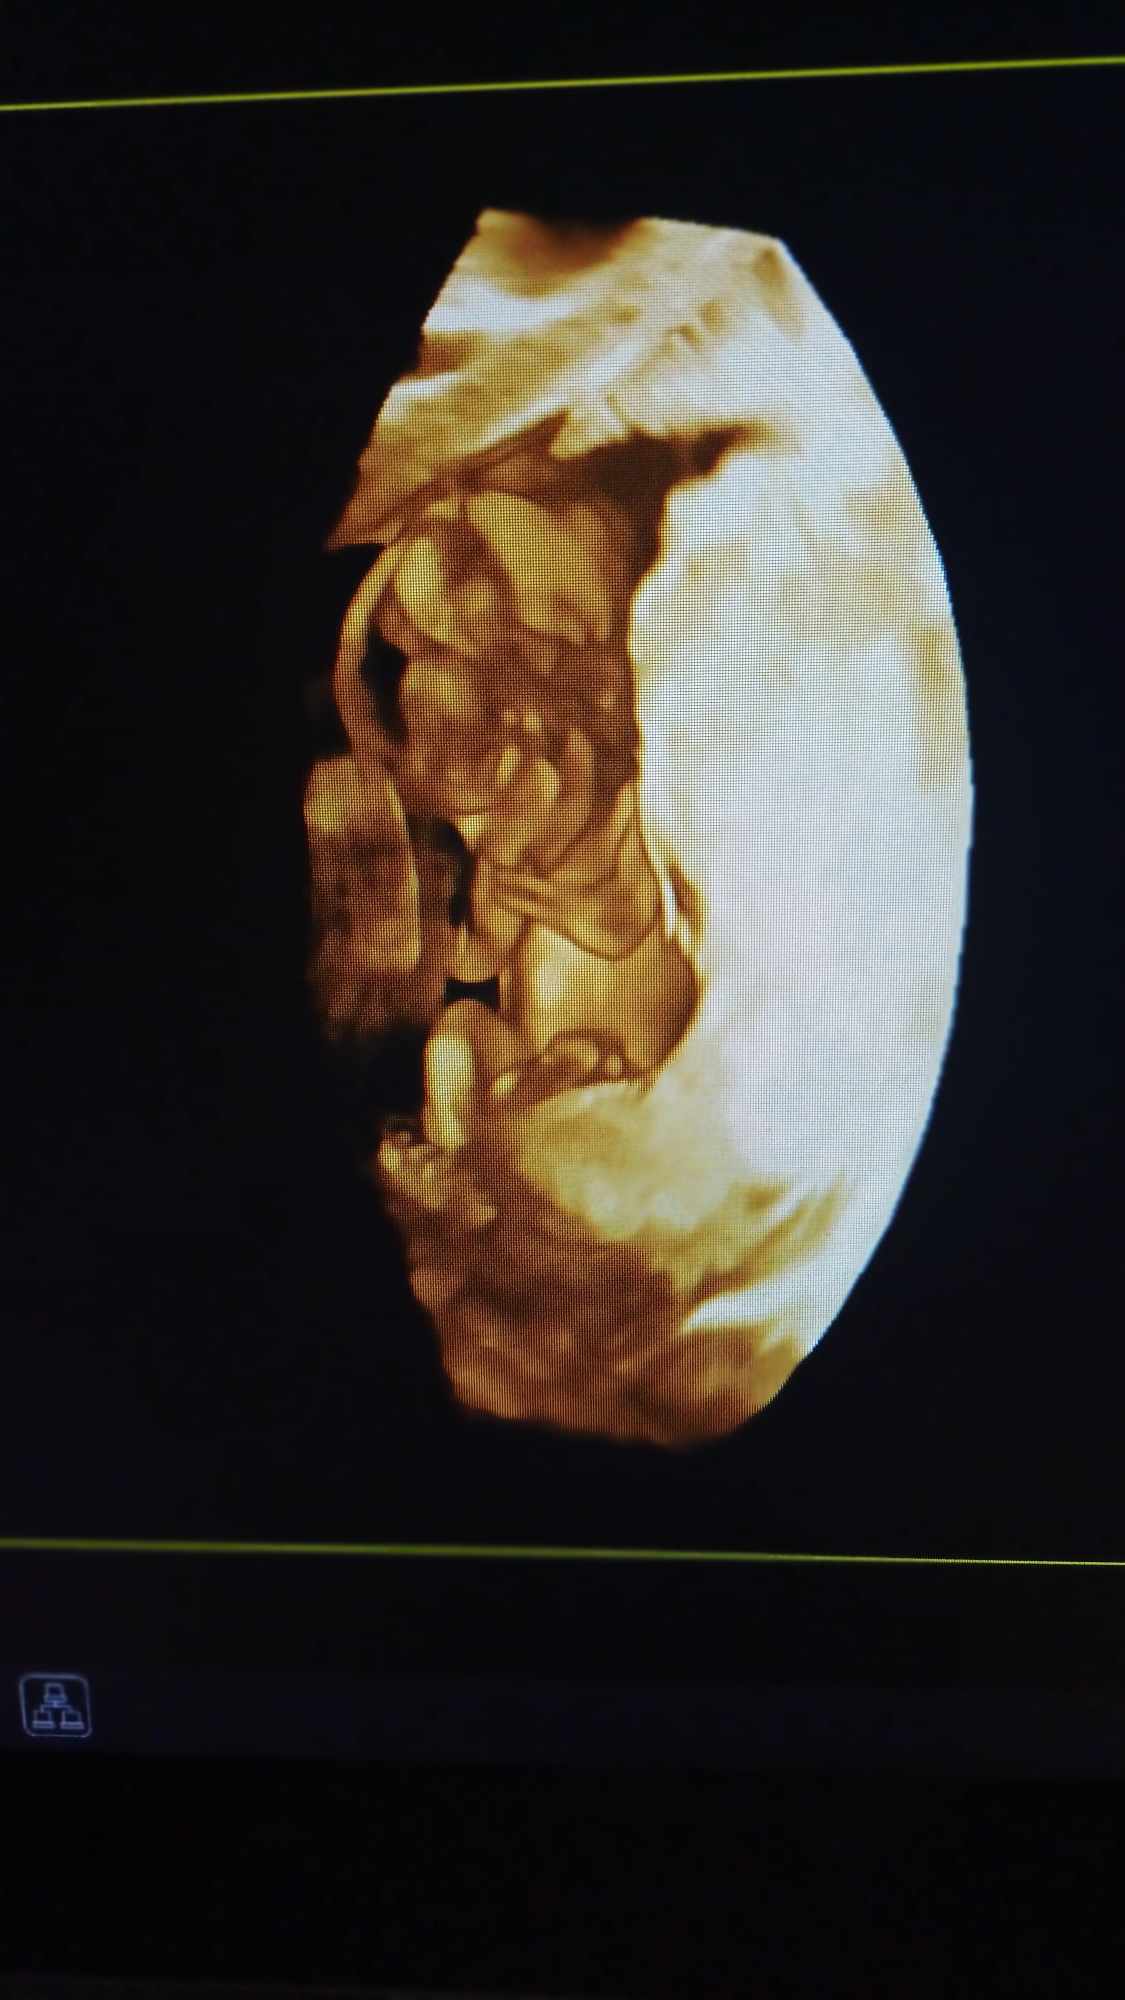

Pozrite si fotky z nášho moderného pracovného prostredia

Naša gynekologická ambulancia je vybavená modernou technikou a poskytuje pacientkom príjemné a komfortné prostredie pre všetky druhy vyšetrení a konzultácií.